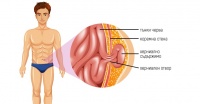

K40.1 Двустранна ингвинална херния с гангрена

С термина hernia се обозначава излизане на чревни гънки през пролука на коремната стена. Двустранна ...

K41 Феморална херния

Феморалната херния е наричана още бедрена херния и представлява излизането на коремни органи през фе...

K42 Пъпна херния

Пъпната херния представлява излизане на коремни органи, покрити с париетален перитонеум през пъпния ...